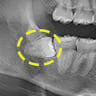

水平埋伏の親知らず

歯茎の中で完全に横に生えてしまうタイプです。

この親知らずを水平埋伏智歯と言います。このタイプはほとんどが下顎のケースです。真横に生えているので抜歯の際は難易度が高く2~3つに砕いて分けて抜歯をします。